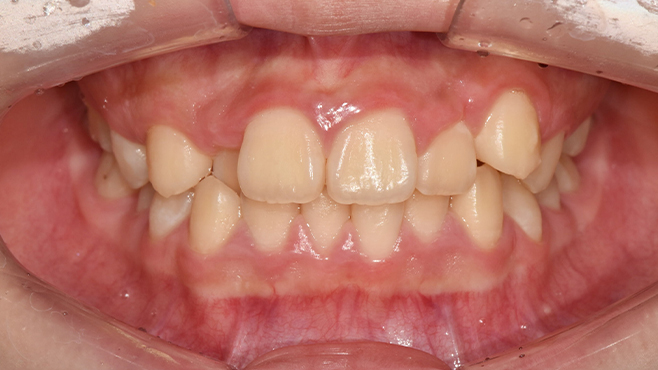

맞는 건 괜찮은데… 충치는 못 참겠습니다|20대 격투기 선수 치과 방문기